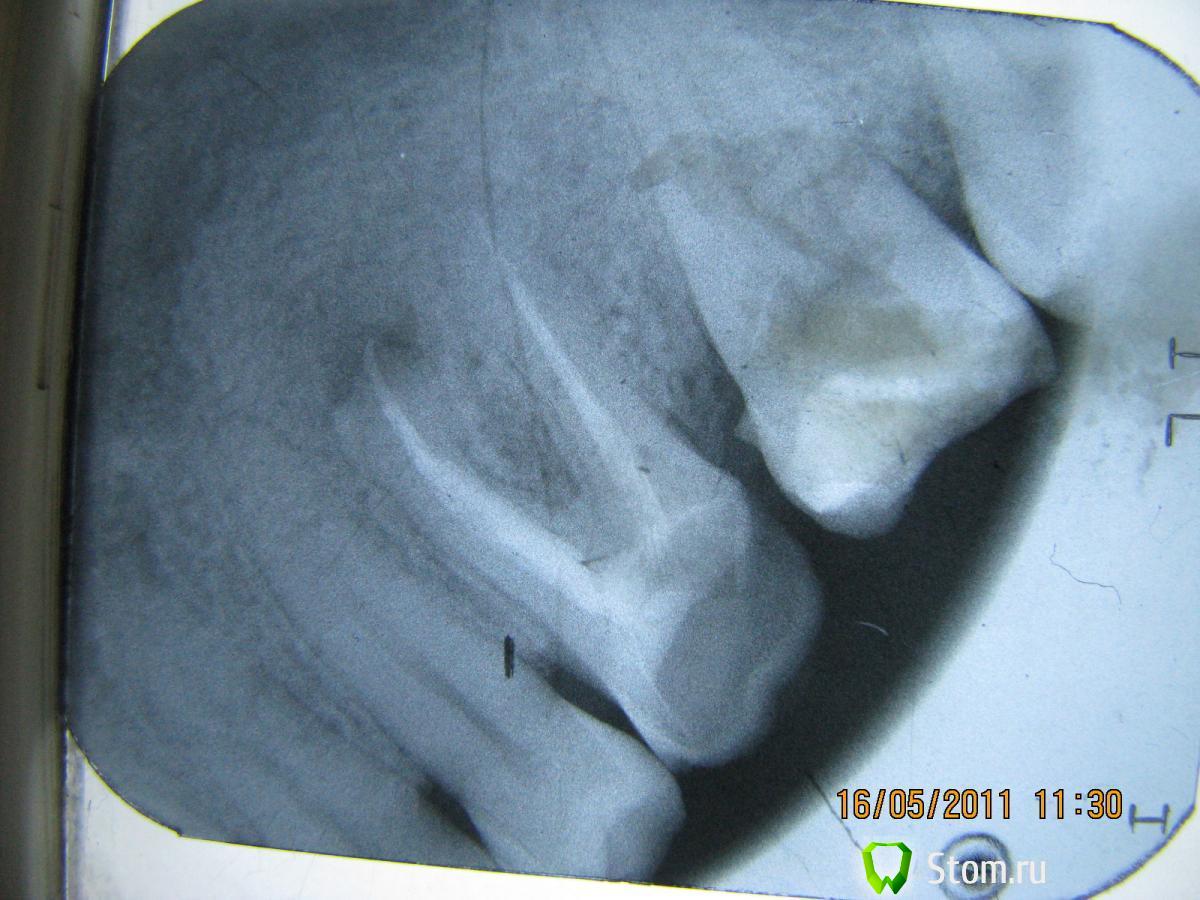

samsonov Опубликовано 15 января, 2012 Поделиться Опубликовано 15 января, 2012 Ну, ладно.Мои 5 копеек.Верите,что у 4.6 обошлось без хирургического вмешательства?Слева- более поздний снимок. Ссылка на комментарий

Kivilgar Опубликовано 15 января, 2012 Поделиться Опубликовано 15 января, 2012 Ну, ладно.Мои 5 копеек.Верите,что у 4.6 обошлось без хирургического вмешательства?Слева- более поздний снимок. Я наверно побоялся бы брать на лечение. Похоже на кисту не связанную с зубом. Вы смелый и удачливый. Ссылка на комментарий

Bobby Опубликовано 15 января, 2012 Поделиться Опубликовано 15 января, 2012 Я наверно побоялся бы брать на лечение. Похоже на кисту не связанную с зубом. Вы смелый и удачливый. Нужно не бояться, а действовать строго по показаниям.Медицина - наука доказательная 1 Ссылка на комментарий

Kivilgar Опубликовано 15 января, 2012 Поделиться Опубликовано 15 января, 2012 Нужно не бояться, а действовать строго по показаниям.Медицина - наука доказательная Ну вот и выскажитесь на счет показаний как ортопед.К samsonov- к лечению приступили без биопсии, ориентируясь на снимок и клиническую картину? Ссылка на комментарий